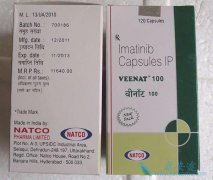

外科手术切除肿瘤是胃肠道间质瘤获得根治性治疗的最佳手段,但术后复发率高达80%。目前,药物治疗胃肠道间质瘤也是一种不错的治疗现在,其中格列卫就是治疗胃肠道间质瘤的有效药物。研究表明,格列卫对复发转移的胃肠道间质瘤具有良好的疗效,已成为标准 ...